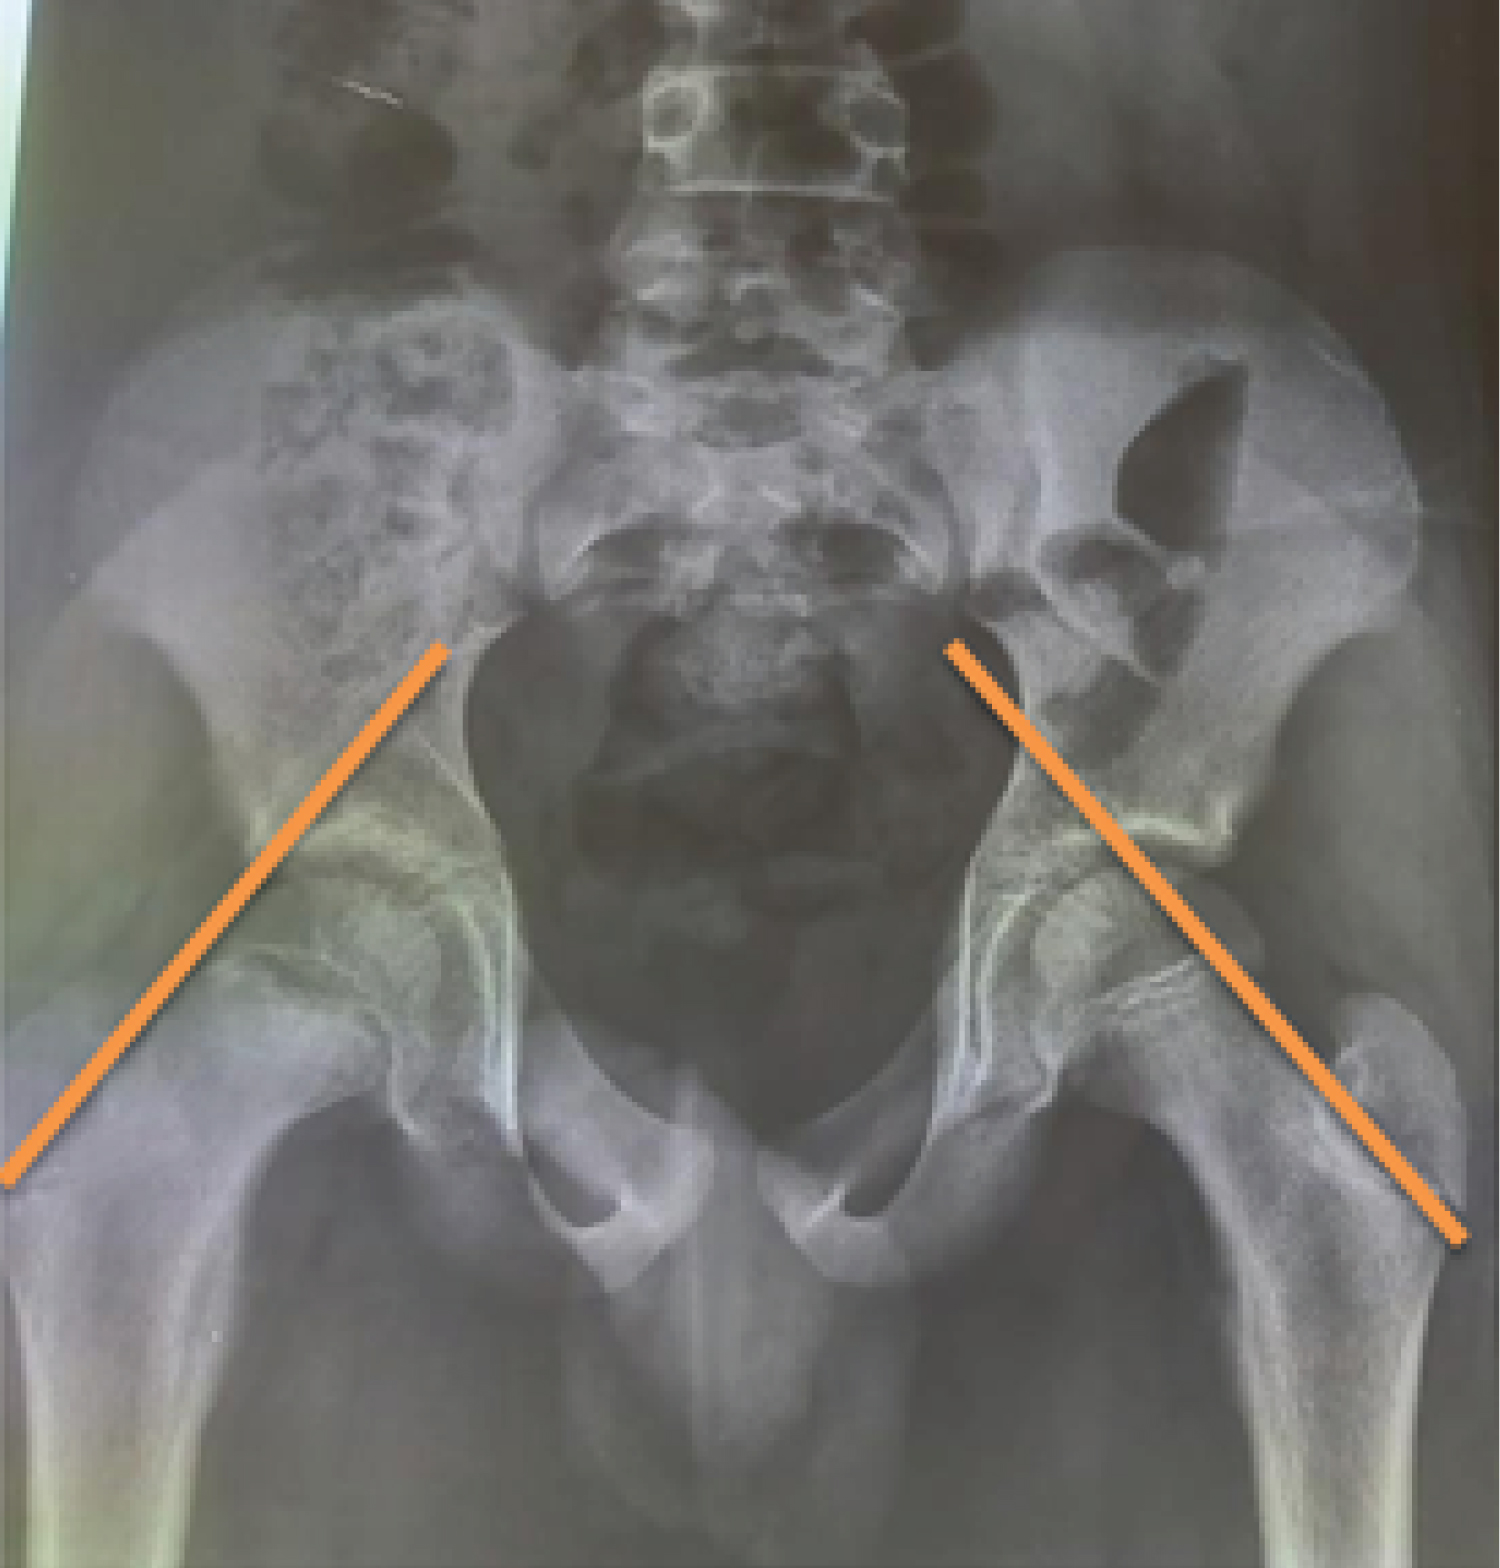

This was a four-year retrospective descriptive study, from January 1, 2017 to December 31, 2020. All patients with upper femoral epiphysiolysis (EFS) treated by simple pinning or percutaneous screw fixation with a postoperative follow-up of at least six (6) months were included. The diagnosis of EFS was established on clinical and paraclinical grounds following a consultation. X-rays of the pelvis and profile enabled us to classify the degree of slippage according to Carlioz. Follow-up was clinical and paraclinical, enabling us to assess post-treatment evolution with a view to detecting and treating complications. On each patient's pelvic X-ray, we determined Klein's line (Figure 1), which is the tangent to the upper edge of the neck, no longer passing through the upper edge of the superior ossification nucleus. On the strict profile X-ray, we traced the SOUTHWICH angle (Figure 2).

75% (6 cases) of our patients were treated with pins (Figure 3) and the remaining 25% (2 cases) with screws. Arroson [4], said that FIS with a single screw is preferable to multiple pins, as it stops the progression of slippage and achieves physeal fusion in 92% of cases. In 2014, Nectoux [5], carried out a study on the outcome of upper femoral epiphysiolysis after in situ screw fixation at a mean follow-up of 11 years, involving 222 cases; this was a multicenter study and the main material used in this series was screws. Unlike other authors, such as Boero, et al. [6] and Seller, et al. [7], who reported the use of pins only in their study? The number of pins used ranged from two to four. Only Boero, et al. [6] used five wires in some of his patients. In our study, the majority of our cases were fixed with two wires, except for one patient who benefited from the use of three wires. This patient had severe stage III slippage. With regard to the configuration of the pin assembly, we used a roughly parallel assembly, like that used by Boero, et al. [6]. By contrast, Seller, et al. [7] used a bouquet configuration with three wires converging at the same cephalic point. The high percentage of wire use in our study may be explained by the accessibility of wires in our departments, their relatively low cost and ease of use. Preventive treatment of the contralateral hip versus its regular monitoring remains a controversial issue. In our series, preventive ECP on the unaffected side was performed in three patients, a rate of (37.5%). One case was treated by screw fixation and the other two by pinning. Stasikelis, et al. [8] determined a method for assessing pelvic skeletal maturity by modifying the Oxford score. The risk of developing a slip on the side of the healthy hip was less than 4% when the triradiate cartilage was closed, zero when the Risser score was 1 or more, and zero when the modified Oxford score was greater than 22. All children who benefited from preventive treatment had a Risser score greater than 1, and the modified Oxford score was 17, 18 and 20. The study by Bernati, et al. [9] provided a number of arguments. According to them, preventive treatment is carried out systematically in cases where close monitoring is contraindicated, and is recommended when the patient is very young in order to avoid limb-length inequality, and when EFS is non-idiopathic. We believe that Bernati's criteria remain the best for preventive fixation of the healthy hip. The complication rate in our series was 37.5%. The evolution of EFS depends on several parameters. Exceptionally, it can also lead to stabilization. Displacement stops when CC welding is complete. We recorded three types of complication: Two coxarthroses and one laminar coxitis. However, we did not find any complications such as intra-articular migration of pins or screws, or infections of the osteosynthesis material. All our patients were assessed using the POSTEL MERLE d'AUBIGNE (PMA) score. The mean PAM score was 15.12 (12 and 18). Overall, we found 50% good and very good results, 12.5% excellent results and 25% fair results. Our results are well below those reported by Violas [3], and Melinda, et al. [10], who found 80% and 93%, but close to those of Falikou [11], and Lawan, et al. [12], who found 62% and 67%. This relatively low rate of our results could be explained by the small size of our sample, the long delay in treatment and the delay in diagnosis. Overall, our results are very satisfactory.

Figure 3: (a) Chronic bilateral unstable EFS; (b) Pin fixation; (c) Complete fusion of growth plate at 8 months post-op. View Figure 3